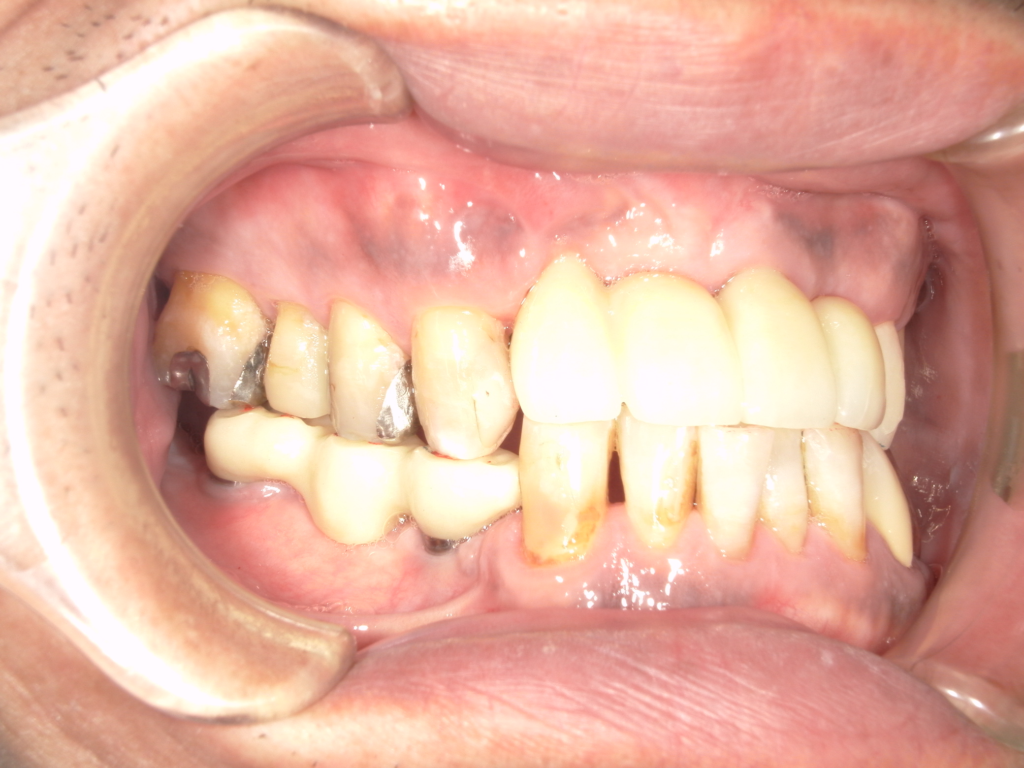

Y様インプラント実例 #44

左の上下の奥歯をインプラントで治療しています。

左下の奥歯は歯を抜くのと同時にインプラントの埋め込みを行っています。

被せものは上下、セラミックスで作っています。

治療前

治療後